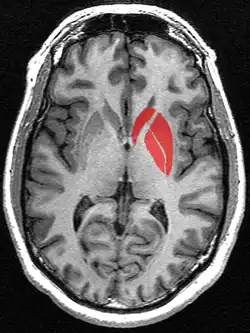

![]() Tractography showing corticostriatal connections | |